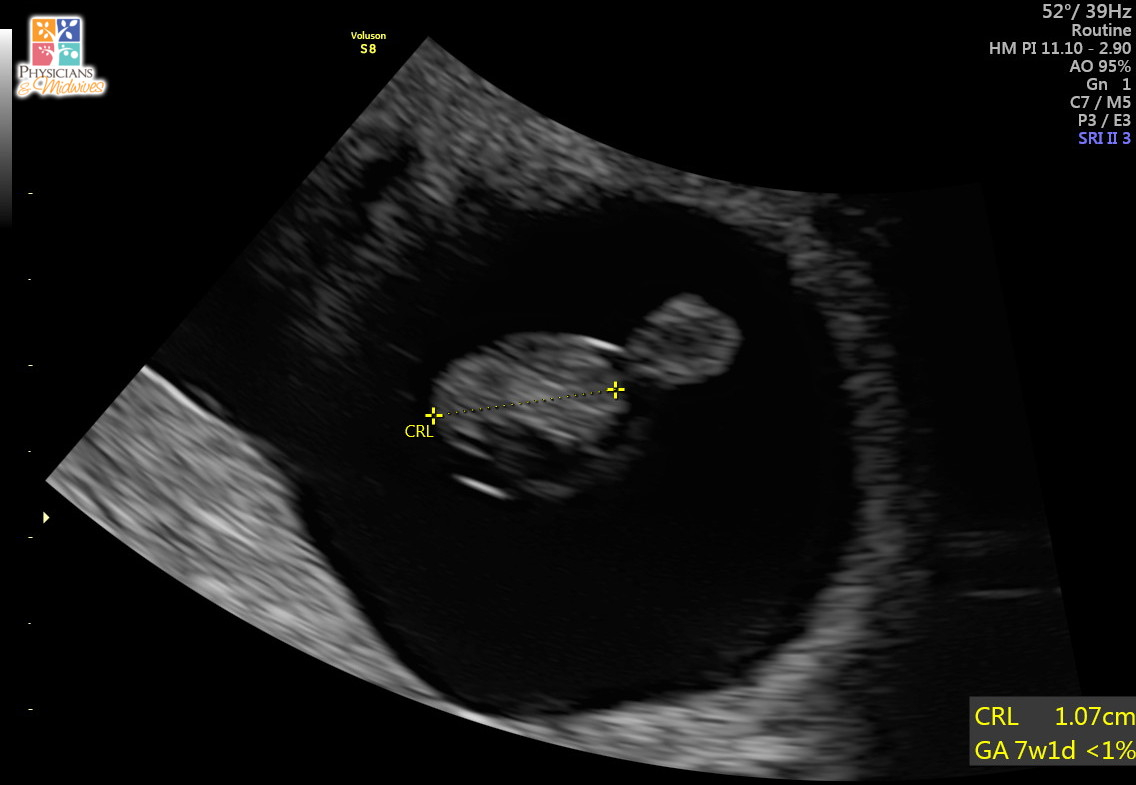

Had our first confirmation US yesterday morning. We were guestimating closer to seven weeks, but babe measured at 6w0d. We couldn't hear the heartbeat, but we could see flutters. We go back in three weeks for another US to confirm everything is progressing normally.